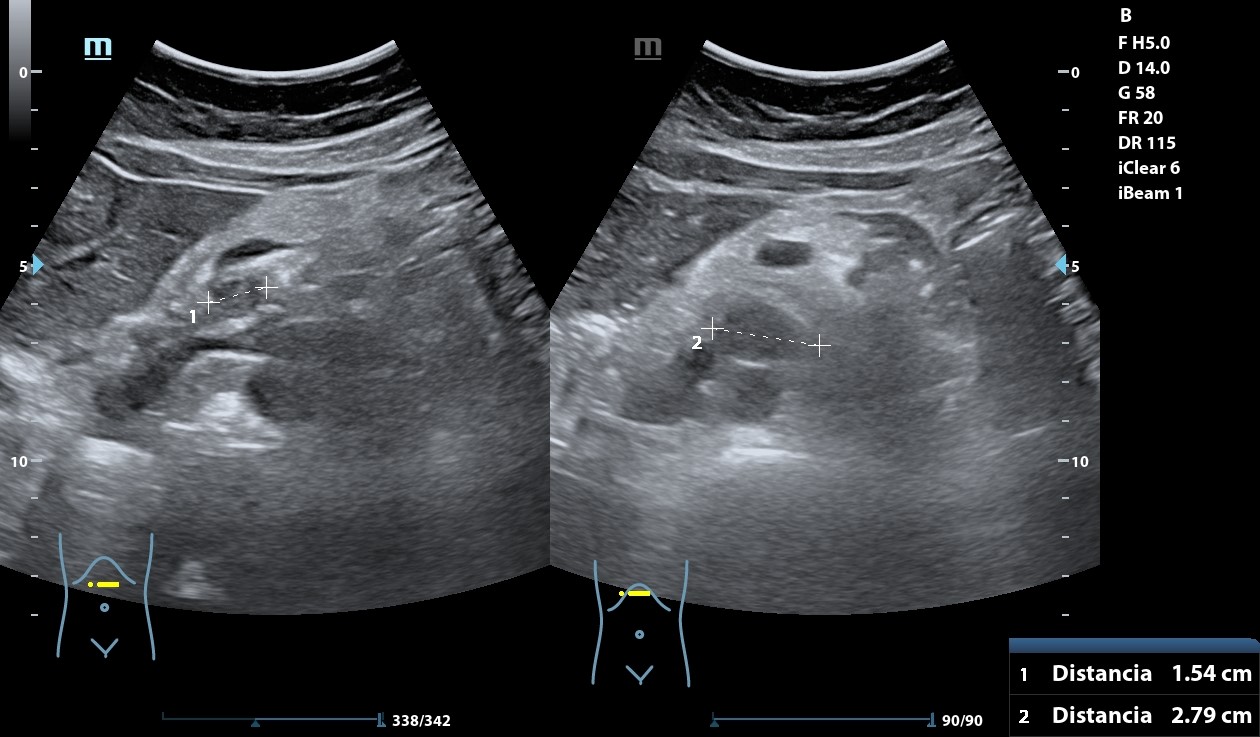

Hígado con abundantes LoEs hiperecogénicas con halo hipoecogénico. Retroperitoneo con abundantes imágenes redondeadas, hipoecogénicas peripancreáticas y retroperitoneales que llegan a medir 28 mm. A nivel de fosa ilíaca izquierda se observa imagen en pseudoriñón que con Doppler presenta captación y llega a medir hasta 72,2 mm.